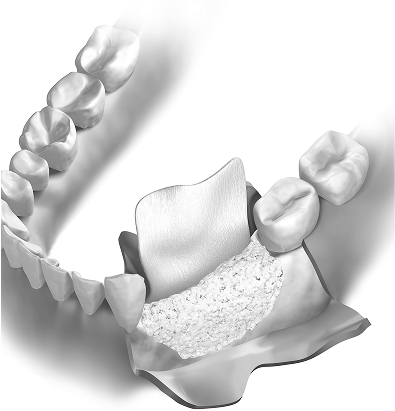

Régénération osseuse guidée

Dans certains cas, une perte osseuse localisée peut être traitée par une greffe osseuse accompagnée d’une membrane, pour stimuler la régénération des structures de soutien. Cette procédure est parfois combinée à un futur traitement implantaire.